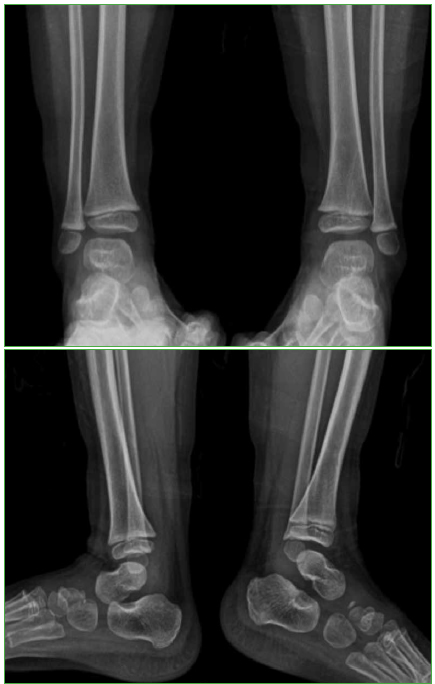

Osteomielitis de tibia secundaria a la vacuna BCG en un paciente pediátrico inmunocompetente. Reporte de un caso

Conclusiones: El compromiso óseo secundario a la vacuna BCG en pacientes previamente sanos es muy raro. Es importante sospecharlo, para diagnosticarlo y administrar el tratamiento adecuado. Se obtuvieron buenos resultados administrando fármacos antituberculosos, sin necesidad de limpieza quirúrgica.